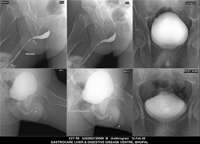

Section: URETHROGRAM

Total: 95 Cases

All Categories BaM Enteroclysis Loopogram BaE Fistulogram Urethrogram HSG